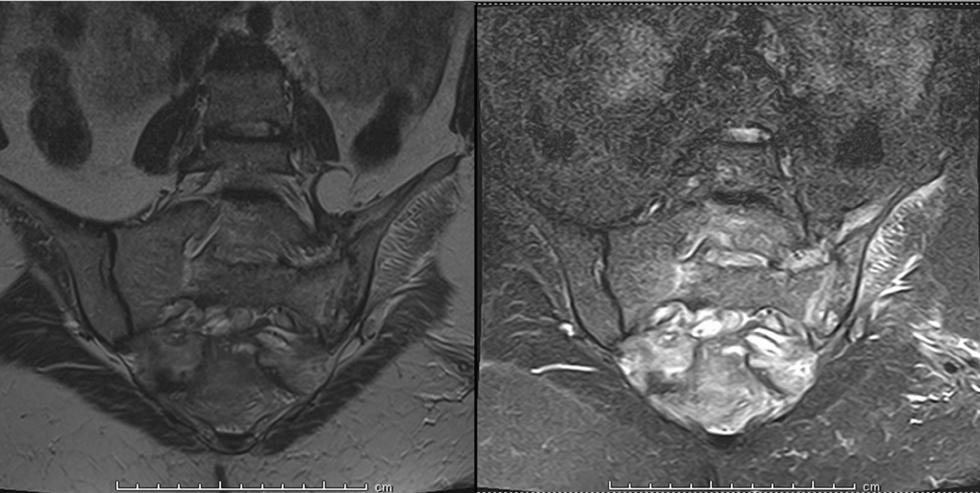

If you like it,why not share it...

Share with a colleague today

Turn static files into dynamic content formats.

Create a flipbook

EMJ 9.4 2024 by European Medical Journal - Issuu